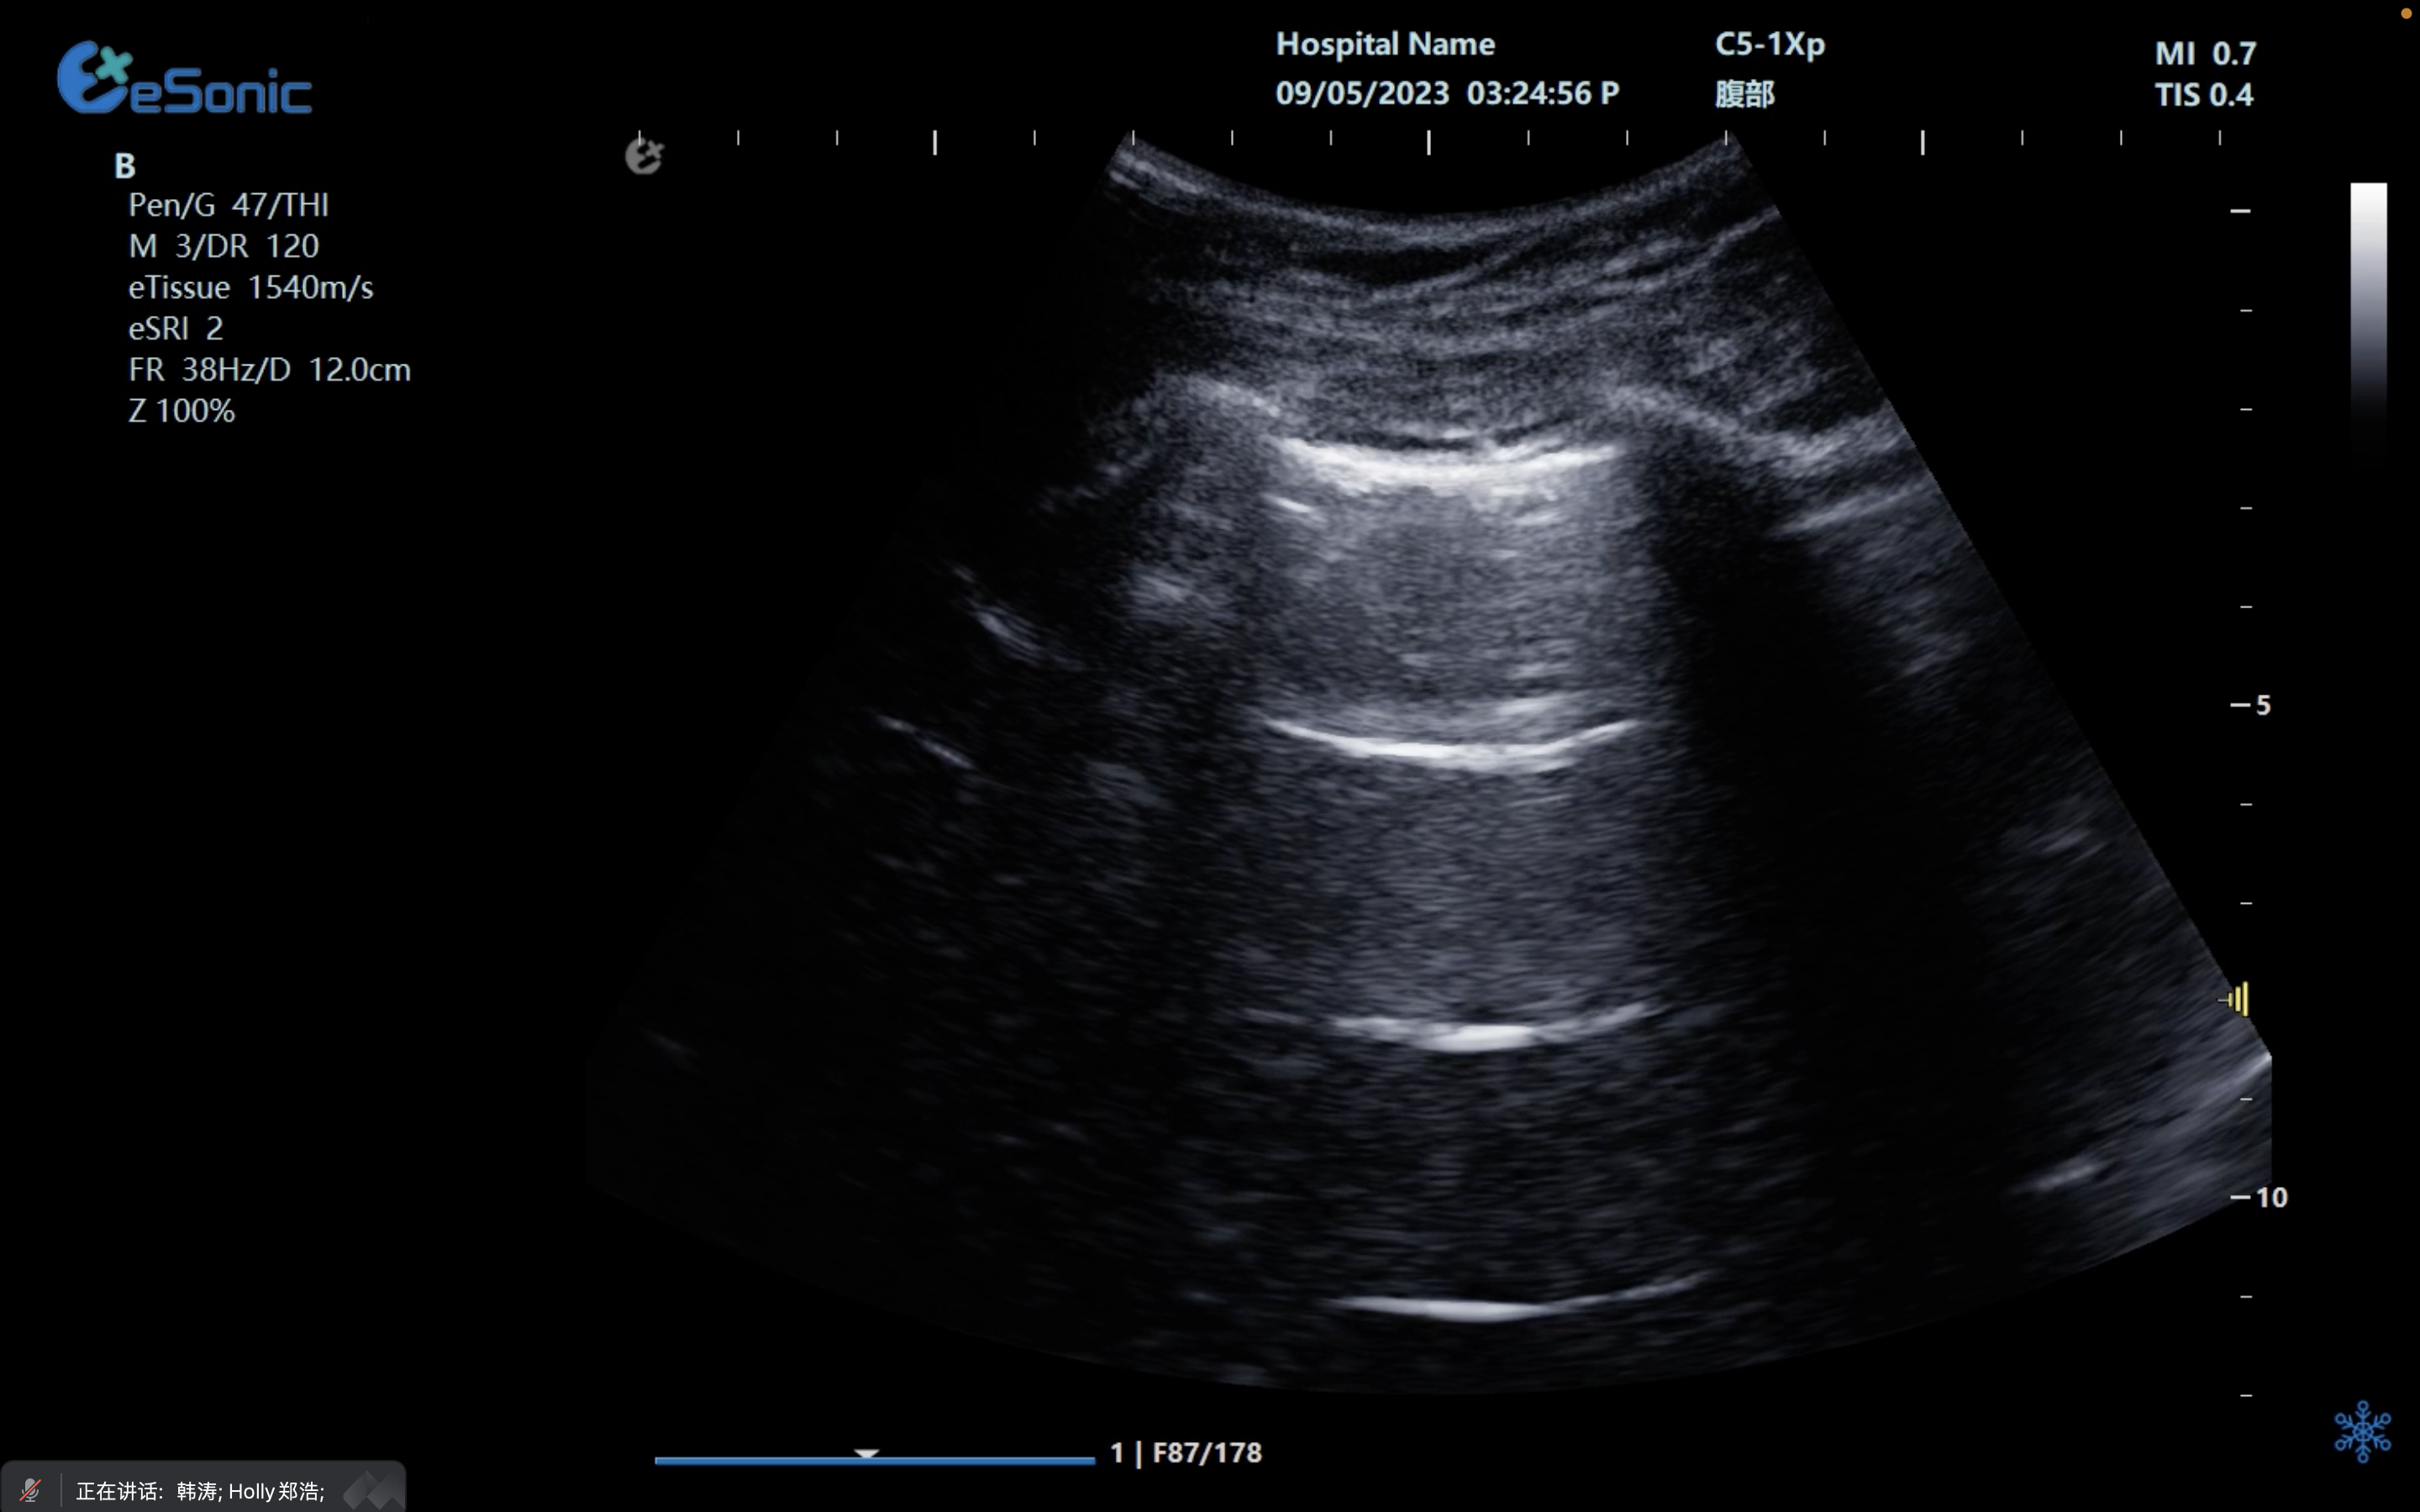

创伤评估FAST

image.png

重症肺部超声

超声声像图:声束垂直胸膜线时,可见多条A线与胸膜线平行,且等间距。